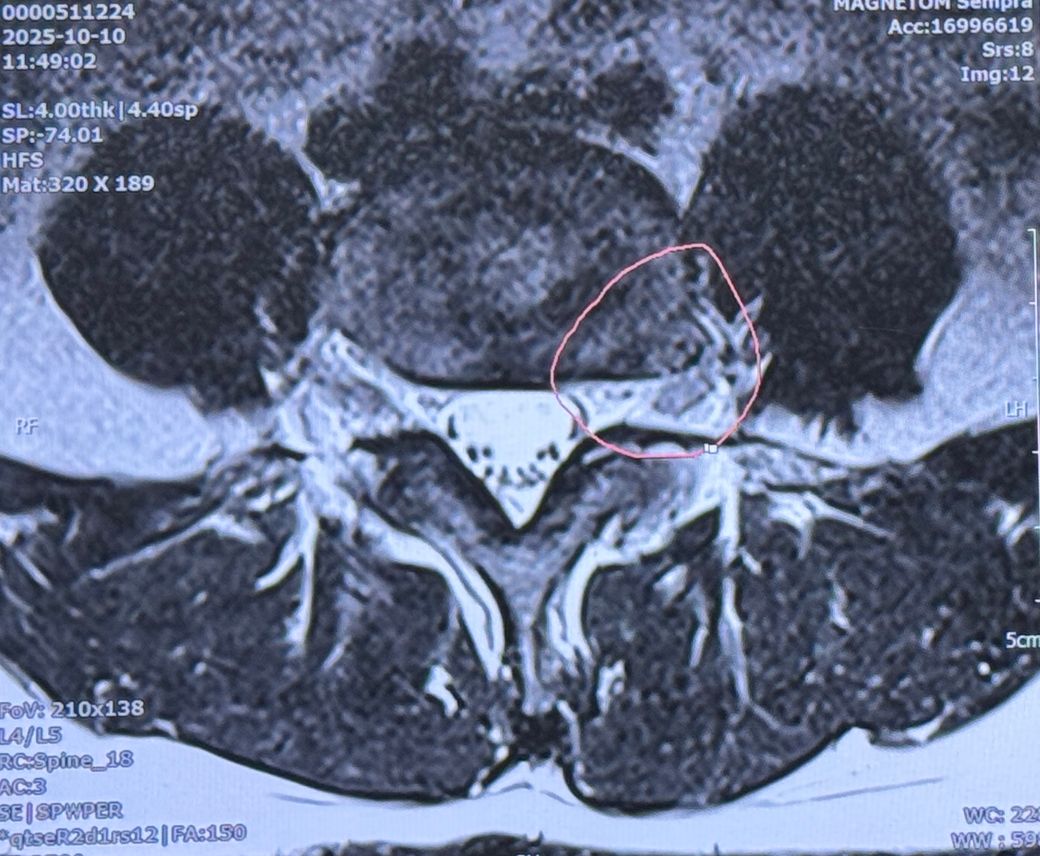

4번째 사진에서 윗쪽 첫번째 뼈 부근도 혹시 터진건가요? 의사쌤이 따로 말씀은 안하셨는데 궁금해서요.

극외측디스크파열이라고 주변에서 그러던데 그게 희귀하다고 하는데 심각한건가요?

외측디스크파열이라고 의사쌤이 말하진 않았습니다.

찾아보니 꼭 수술해야한다고 하는데 혹시 MRI판독 부탁드랴도 될까요?

• 4번 째 사진